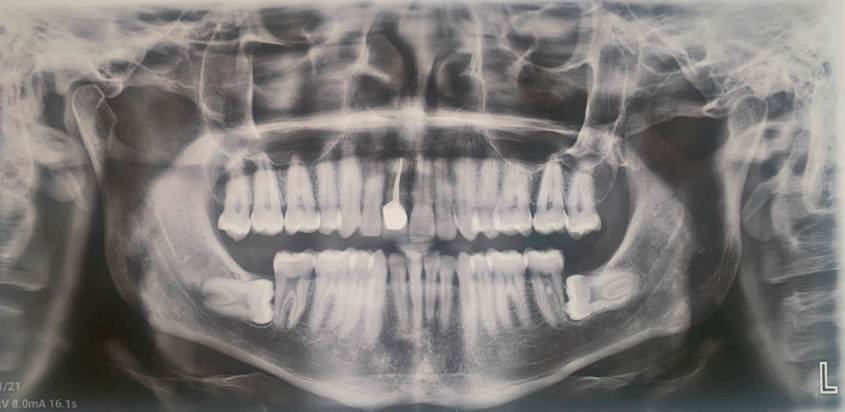

Al finalizar el tratamiento de ortodoncia se retiraron los aparatos fijos y se colocaron retenedores. En ortopantomografías y laterales de cráneo, se puede identificar la salud periodontal y endodóntica del diente trasplantado, así como la integridad radicular.

En este caso no se encontraron cambios oclusales y el índice de irregularidad fue de 2 mm en la arcada inferior, según se evaluó después de 12 años de finalizado el tratamiento. Se lograron relaciones de clase I en molares y caninos en ambos lados, la sobre mordida horizontal y vertical fueron ideales. El seguimiento a largo plazo (12 años) del diente trasplantado en el sitio del diente 11, se ha mantenido estable y funcional (Figura 6). La raíz del diente trasplantado se encontraba con hueso cortical deficiente al inicio del tratamiento, por lo que durante todo el tratamiento se utilizaron fuerzas ligeras para evitar la reabsorción de la raíz y obtener la máxima estabilidad (Figura 7).

Los valores cefalométricos de pretratamiento, postratamiento y evaluación cefalométrica 12 años después del tratamiento de ortodoncia están en la Tabla 1. Las superposiciones entre los tres trazados cefalométricos muestran cambios en las medidas cefalométricas al comienzo de T1, T2 y T3. El análisis cefalométrico postratamiento destaca efectos dentarios, con retro inclinaciones de la arcada superior e incisivos inferiores, modificando también un aumento del ángulo interincisal. En la evaluación a los 12 años del tratamiento no se observan cambios en la posición de los incisivos superiores e inferiores (Figura 8).